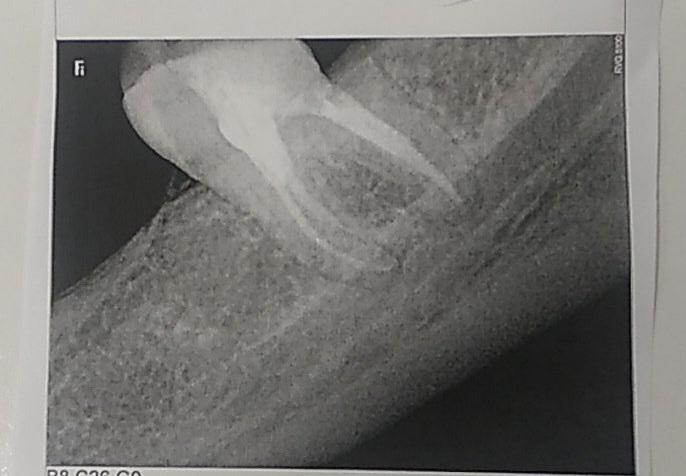

Если рассматривать этот зуб,как отдельно стоящий(и если есть антагонист на в/ч ), то в принципе можно сделать вкладку(при условии хорошей изоляции,учитывая,что уровень дистального корня на границе с десной),а затем и коронку,конечно.

А включать этот зуб в конструкцию(мостовидный протез или съёмный ,с опорой на него) я бы не стала.

Анна Адеева, ортодонт сказал что из за того что он сломан со стороны десны